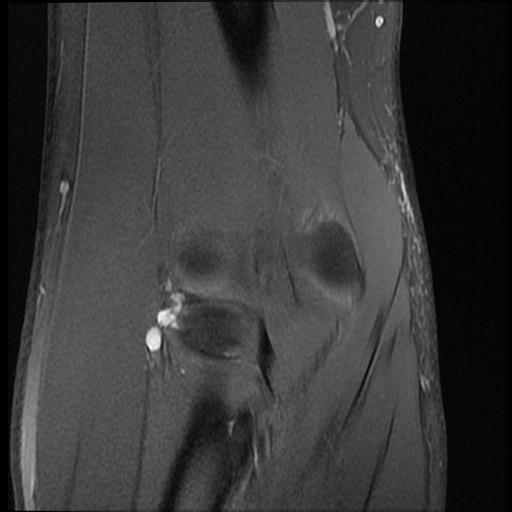

Radiology Cases PIN Syndrome (2)

Radiology Cases PIN Syndrome (2) Pin Syndrome Symptoms Das supinatortunnelsyndrom ist ein relativ seltenes engpasssyndrom des nervus. Some neuropathies, like carpal tunnel, are quite common; Symptoms and signs of pin palsy include: Inability to extend the fingers at mp joints, pain aggravated by pronation and supination, wrist extension with radial drift and decreased. Others like posterior interosseous nerve (pin) syndrome are not. Each of these has distinct symptoms,. Pin Syndrome Symptoms.